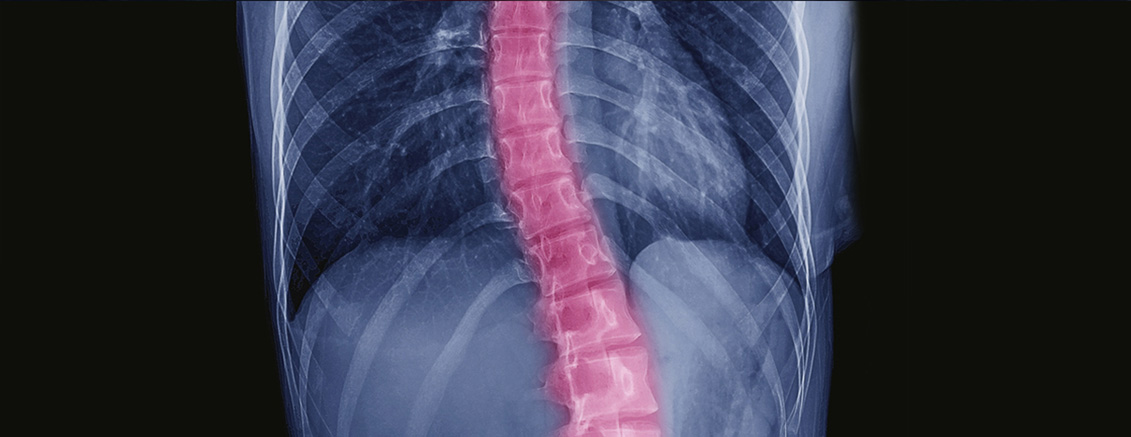

Á¤»óÀûÀΠôÃß´Â Á¤¸é¿¡¼ º¸¾ÒÀ» ¶§ ÀÏÁ÷¼±ÀÌ¸ç ¿·¿¡¼ º¸¾ÒÀ» ¶§¿¡´Â °æÃß¿Í ¿äÃß´Â ¾ÕÀ¸·Î ÈÖ°í(Àü¸¸°î) ÈäÃß¿Í ÃµÃߺδ µÚ·Î ÈÖ¾î(Èĸ¸°î) ÀÖ´Â ÇüÅÂÀÔ´Ï´Ù. ôÃß Ãø¸¸ÁõÀº ôÃß°¡ Á¤¸é¿¡¼ º¸¾ÒÀ» ¶§ ¿·À¸·Î ÈØ °ÍÀ» ÁöĪÇϳª, ½ÇÁ¦·Î´Â ´Ü¼øÇÑ 2Â÷¿øÀû º¯ÇüÀÌ ¾Æ´Ï¶ó ôÃß»ÀÀÇ È¸ÀüÀÌ µ¿¹ÝµÇ¾î ¿·¿¡¼ º¸¾ÒÀ» ¶§¿¡µµ Á¤»óÀûÀÎ ¸¸°î »óŰ¡ ¾Æ´Ñ 3Â÷¿øÀû º¯ÇüÀ» ¸»ÇÕ´Ï´Ù.